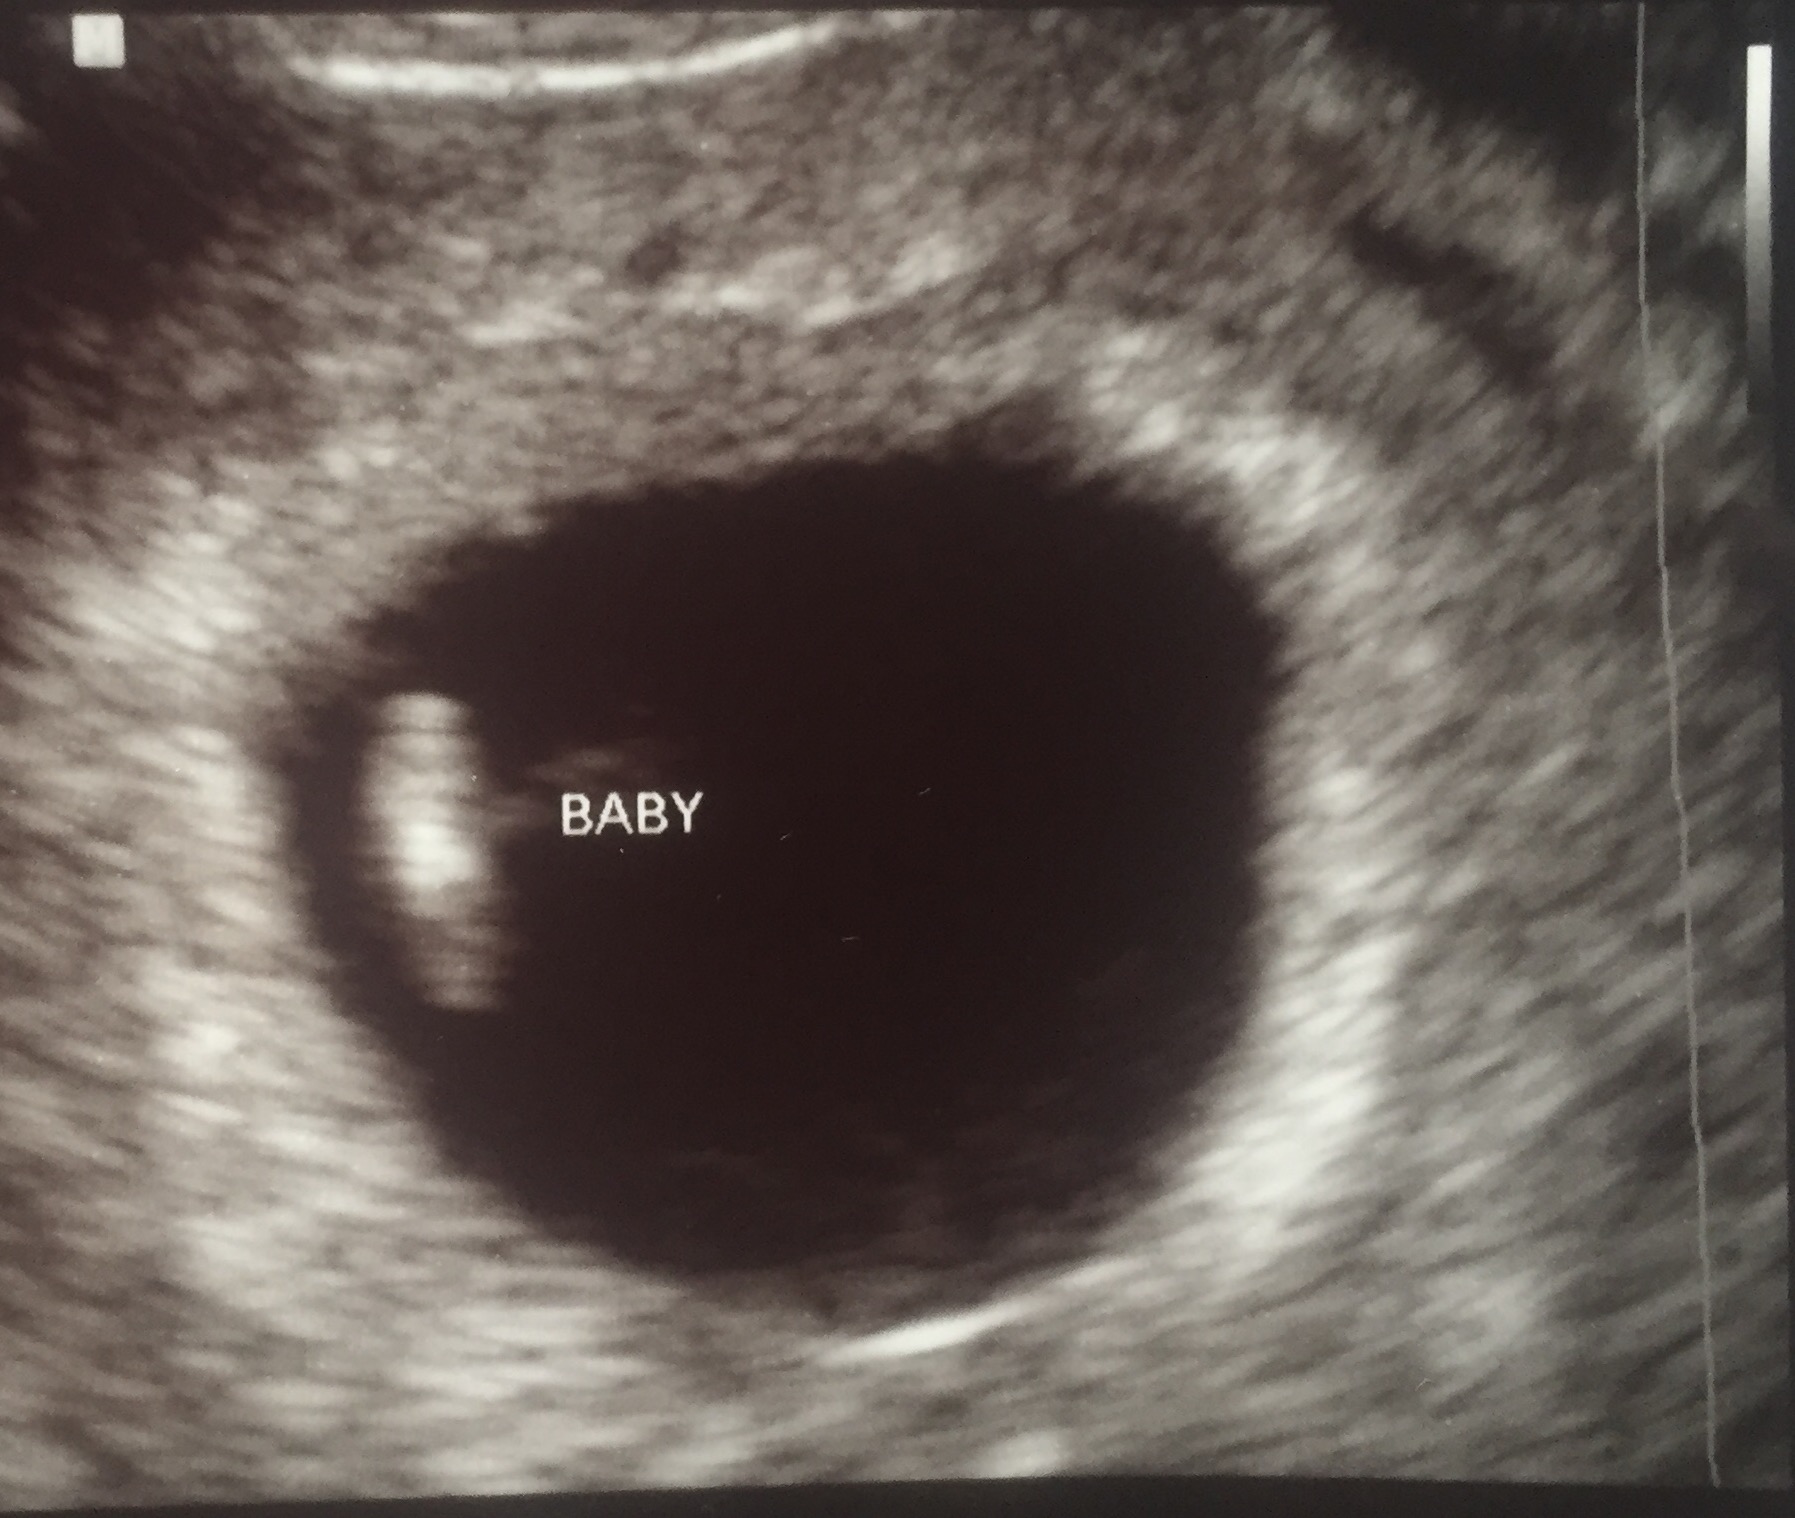

My little bean. According to LMP I was 6wks+5d but baby is measuring 6wks+3. They aren't changing my date yet because the baby is so small the tech said she wasn't sure she was even measuring the whole baby. Hb was 118. I had a 2nd trimester MC in May so I'm going to get to see this bean a lot! ☺️